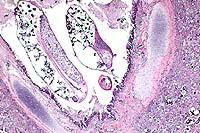

Contributor's Diagnosis and Comments: 1. Severe, subacute to chronic, lobular, eosinophilic, interstitial pneumonia and bronchiolitis with intrabronchiolar nematode parasites and intra-alveolar eggs containing larvae, lung. 2. Severe, subacute, fibrinous pleuritis, lung.

Metastrongylus is the only genus found in the family Metastrongylidae. All species are large white parasites of the bronchi and bronchioles of swine and the three most important species of this genus are M. apri, M. pudendotectus, and M. salmi. The intermediate host for these parasites is the earthworm. The oviparous females lay eggs containing the first stage larvae which are then passed in the feces of infected swine. The eggs do not hatch or develop into infective larvae unless they are ingested by an earthworm. In the earthworm, the larvae develop to the third, infective stage in approximately 10 days and remain quiescent unless the earthworm is eaten by a pig. Migration in the pig is through the lymphatics from the intestine to the lungs. In this case, the interstitial pneumonia and bronchiolitis in this pig may be the result of both the Metastrongylus parasites, as well as migration of Ascaris suum larvae due to the heavy ascarid load.

Nematode parasites found in the lungs of other mammalian species include:Dictyocaulus filaris (sheep, goats, other small ruminants), D. viviparous (cattle) and D. arnfieldi (horses, donkeys), Protostrongylus rufescens (sheep, goats, deer), Muellerius capillaris (sheep, goats), Crenosoma vulpis (foxes), Filaroides hirthi(dogs), Aelurostrongylus abstrusus (cats), and Angiostrongylus vasorum (dogs, foxes).